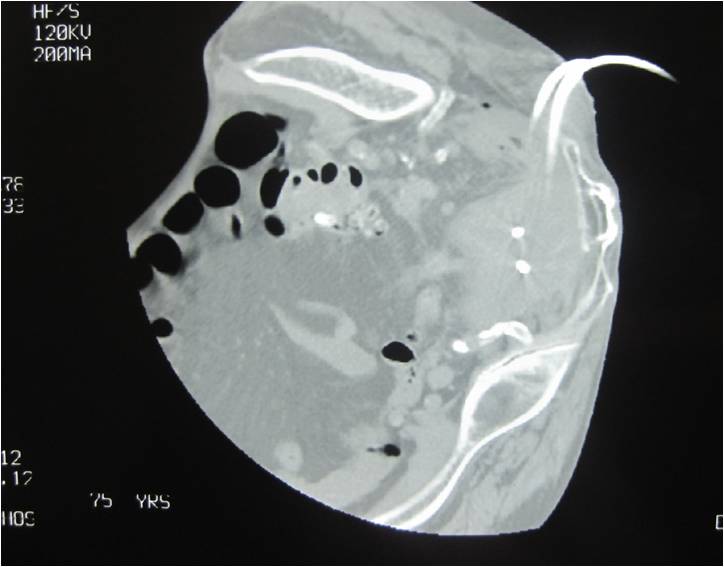

- Placement of a nephrostomy and sump caheter through the greater sciatic foramen into a deep pelvic abscess.